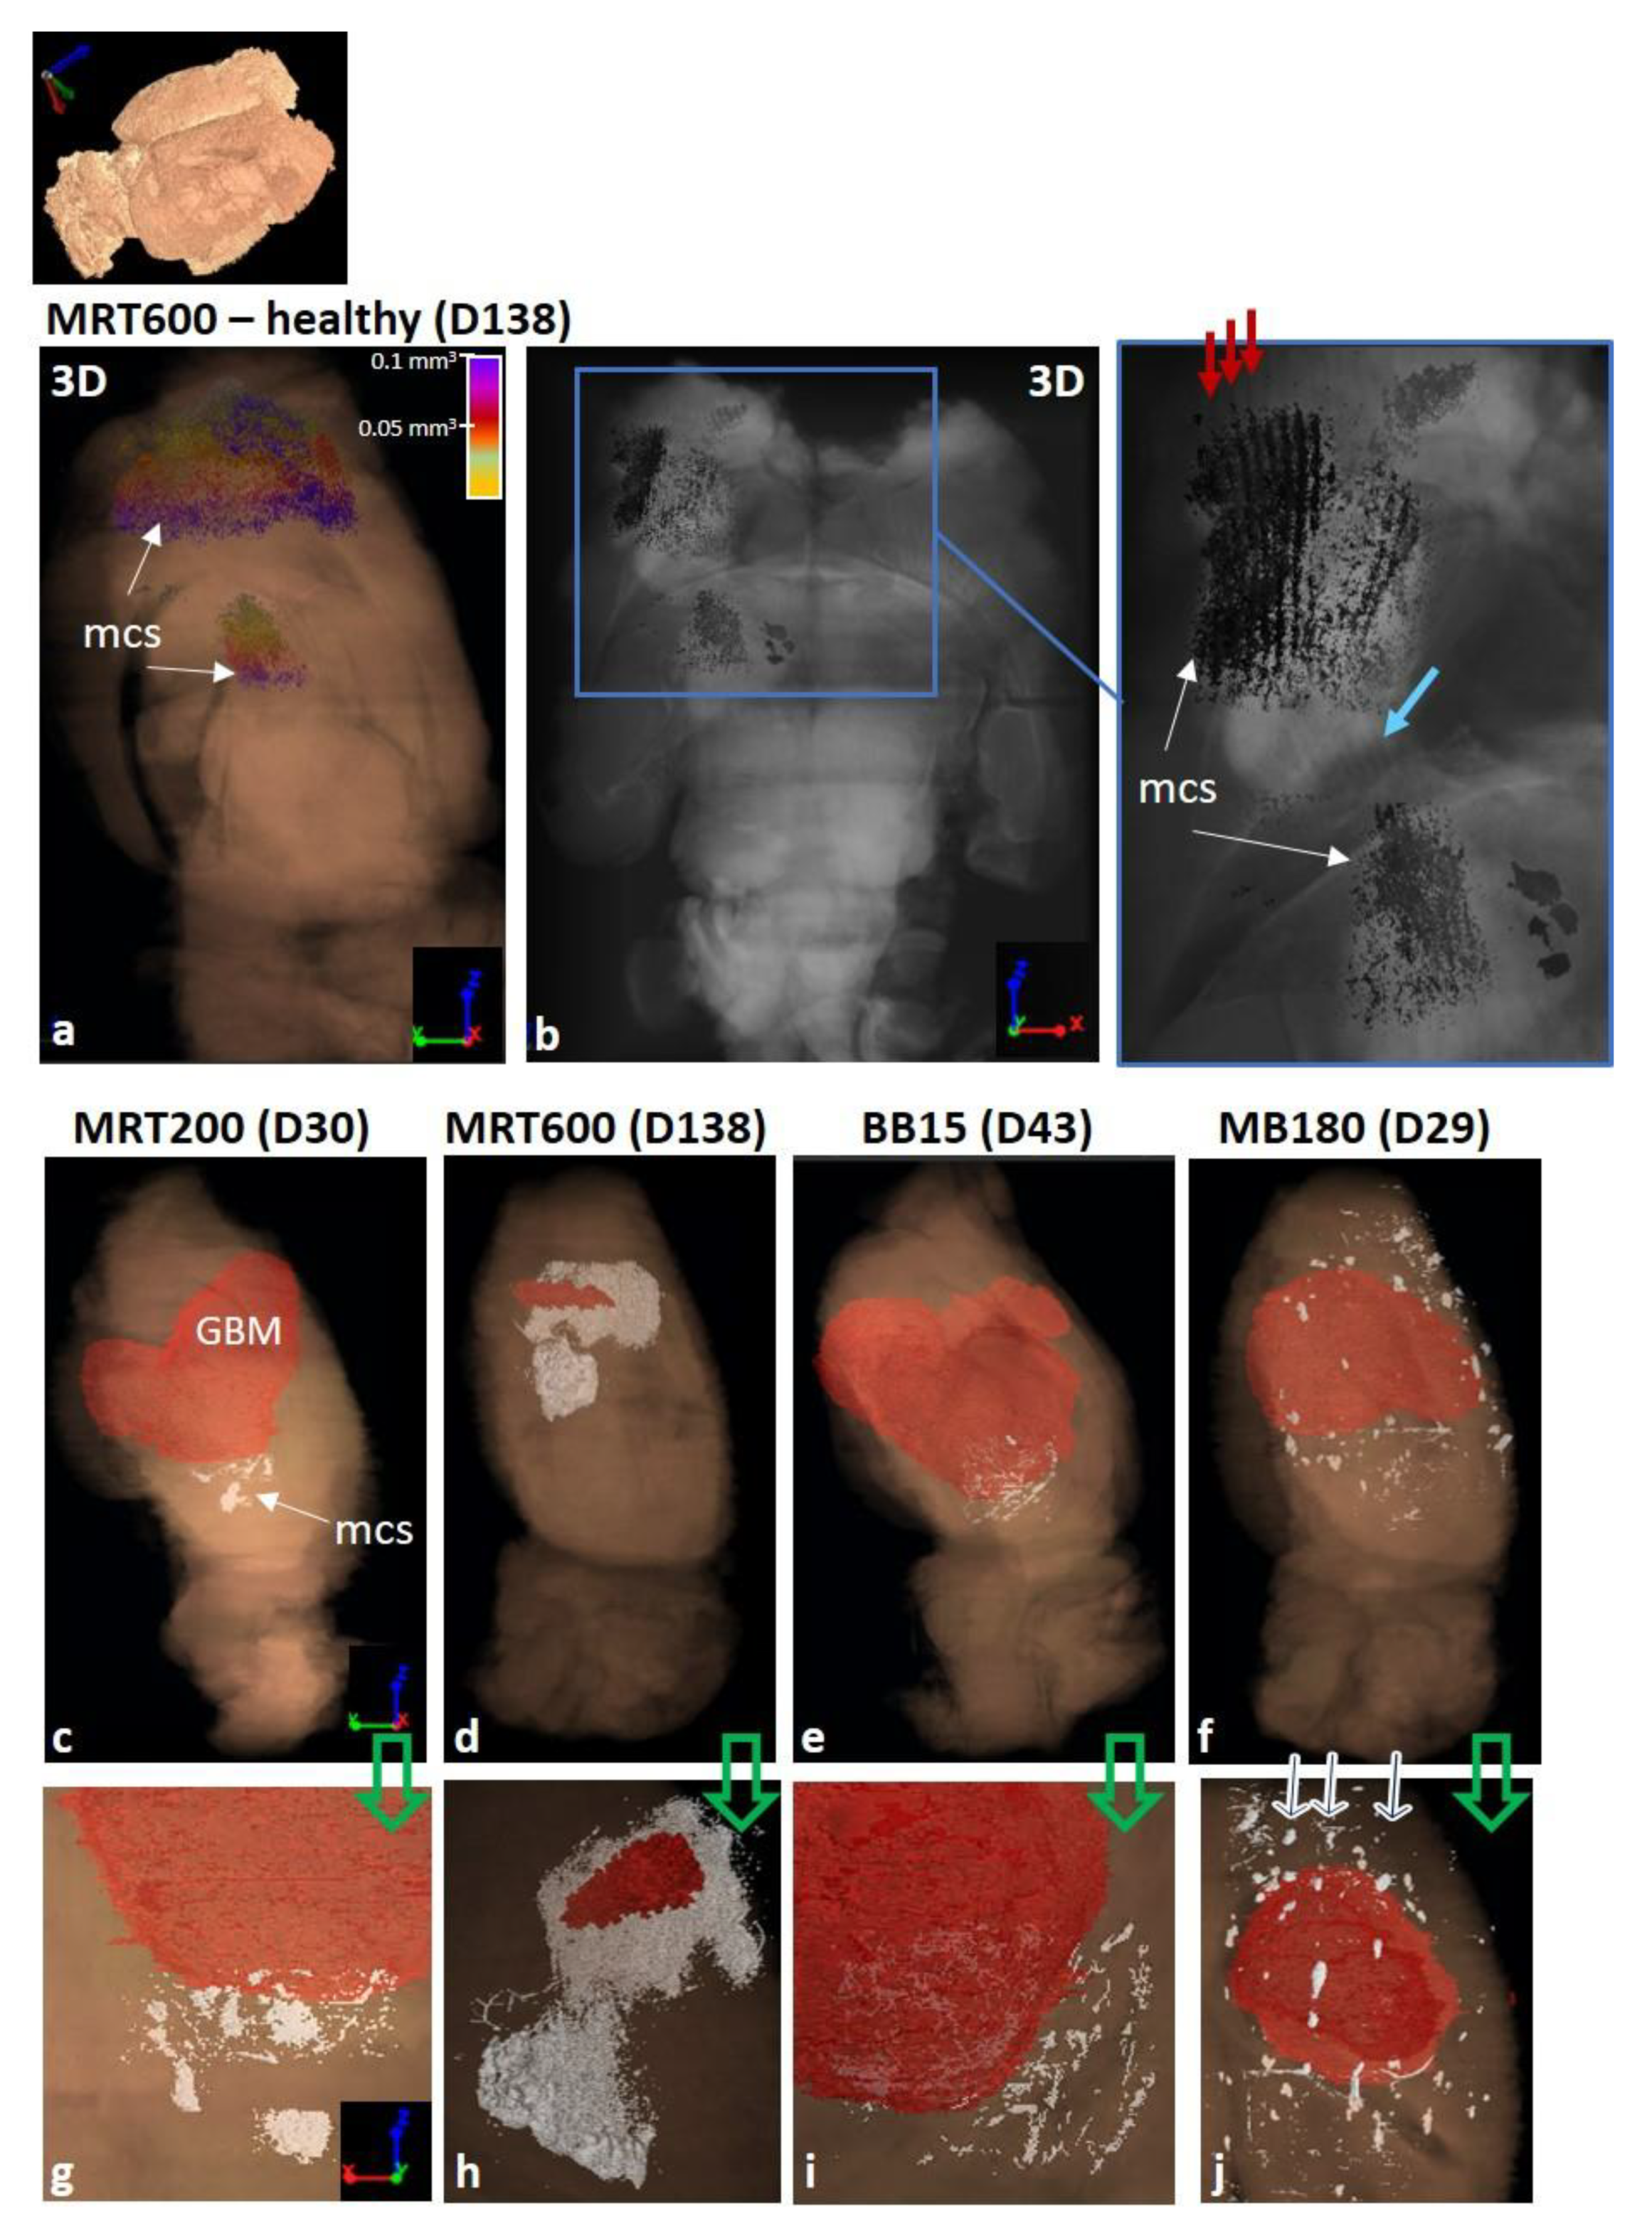

3.3. Quantification and 3D Rendering of Radiotherapy Effects

4.4. A Full 3D Characterization and Quantification of RT-Induced Effects